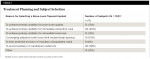

Reasons for tooth loss varied among subjects with most (72%) being due to fractured teeth and caries. The majority of subjects (65%) had no existing implants at baseline; 35% of subjects had from one to 10 existing implants at baseline. The study population represented a typical private practice distribution of missing dentition, from zero to fully edentulous. Selection criteria for treatment planning with the BLT implant are outlined in Table 1.

The majority of implants (54.9%) were immediately placed (type 1 placement) with 9.6% of the immediately placed group immediately loaded. Table 2outlines details surrounding these parameters. Sixty-four implants were placed in the premolar region, 60 incisor, 43 molar, and 17 cuspid, representing a broad distribution of implant placement. Table 3details loading categories and corresponding restoration types.